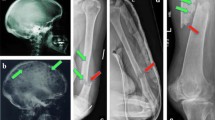

8.1.1 Diagnosis

Myeloma bone disease is diagnosed through the use of plain radiograph, whole body low dose computed tomography, or whole body magnetic resonance imaging skeletal surveys to detect the presence of osteolytic bone lesions [6]. Plain radiograph is the least sensitive available type of imaging, as a bone lesion needs to be at least 1 cm in size and associated with at least 30% loss of bone mineral content before it can be detected [7]. Despite this, most current guidelines recommend plain radiograph skeletal survey as the primary method for the detection of MBD, followed by the utilization of other modalities if there is a suspicion of MBD and conventional radiography is negative [3, 8]. Imaging findings such as osteoporosis, osteopenia, or compression fractures without the presence of osteolytic lesions is insufficient to meet the current criteria for MBD [6]. The IMWG has also noted that increased fluorodeoxyglucose uptake on positron emission tomography (PET) scan without an associated destructive bone lesion does not meet the criteria for MBD [3].

8.4.1.7 Subtrochanteric and Other Atypical Femoral Fractures

The symptoms of atypical femoral fractures can be subtle and preceded by thigh or groin pain prior to diagnosis [31]. Long-term bisphosphonate use is linked to the development of atypical femoral fractures in approximately 93.9% of cases [41]. The majority of atypical femoral fractures occur at the proximal femur, with a minority occurring at the subtrochanteric region along the femoral shaft [42].